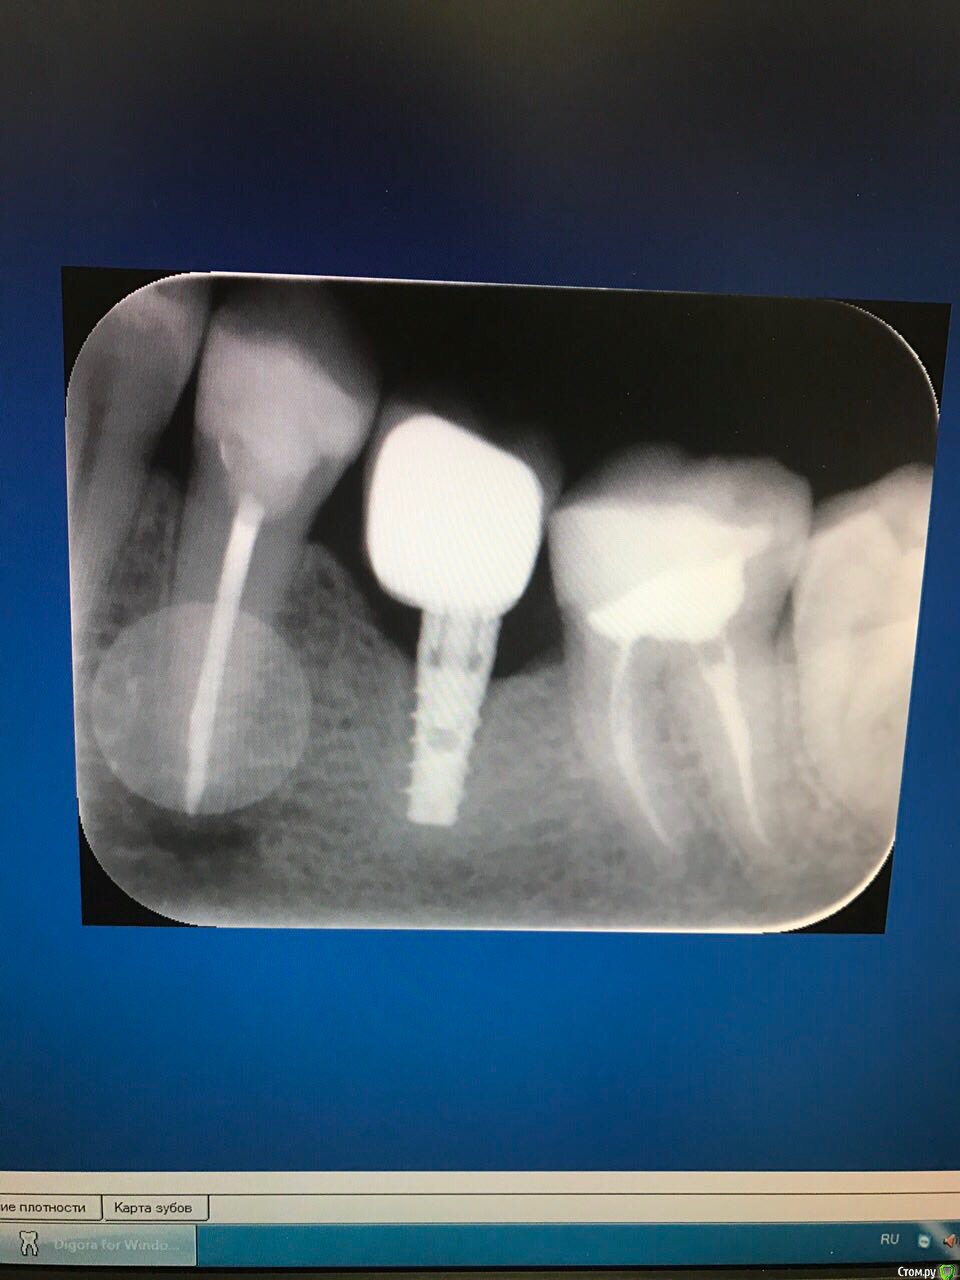

AnnaMag Опубликовано 19 июля, 2017 Поделиться Опубликовано 19 июля, 2017 (изменено) В январе 2015 установили 2 импланта на нижние жевательные зубы ( в подростковом возрасте ставили брекеты и эти зубы разрушились постепенно). Уровень кости был ниже обычного, так как (2 нижних шестерок) не было уже некоторое время. На этой неделе стала ощущать неприятные ощущения при жевании на правой шестерке. При давлении на коронку (под которой имплант) также иррадиирующие неприятные ощущения.Иногда бывает как будто тянет. Отека/покраснения на десне нет.Врач, который ставил коронку, видимо, в отпуске (не отвечает). Пожалуйста, посоветуйте, что предпринять в данном случае.Ниже рентген. Спасибо! Изменено 19 июля, 2017 пользователем AnnaMag Ссылка на комментарий

AndyAndy Опубликовано 19 июля, 2017 Поделиться Опубликовано 19 июля, 2017 По снимку смущает пролеченный 5-ый зуб, там воспалительный процесс прослеживается на верхушке корня. По поводу коронки на имплантате - нужен ещё и очный осмотр, оценить десну. Было бы неплохо сравнить снимки той давности, когда устанавливали имплантат Ссылка на комментарий

dok1 Опубликовано 19 июля, 2017 Поделиться Опубликовано 19 июля, 2017 Если присмотреться, несколько крупных витков резьбы импланта не касаются кости. И шейка коронки начинается с платформы импланта. Отсутствует платформа абатмента. Всё это, на мой взгляд, говорит о проблеме именно от импланта. Думаю, топикстартер прав - ход мыслей о причине дискомфорта вращается вокруг имплантированного зуба. 2 Ссылка на комментарий

Bier Опубликовано 23 июля, 2017 Поделиться Опубликовано 23 июля, 2017 я о том, что если имплантат болит при накусывании, то либо вы путаете зуб, что тоже возможно, либо в конструкции есть механические проблемы. Типа трещины или раскрученного винта абатмента. Т.к. судя по снимку имплантат у вас неподвижен.Болезненненная перкуссия говорит о том, что что-то куда-то движется и на что-то давит, вызывая боли. Осталось выяснить что. Ссылка на комментарий